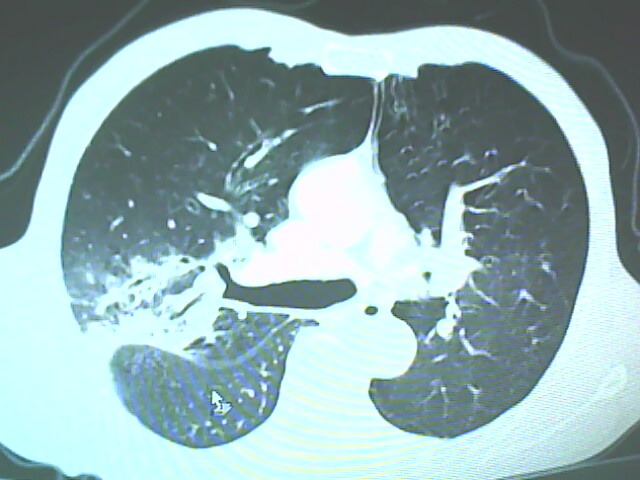

患者,男,66岁,以咳嗽、咳痰伴胸痛来就诊。

胸片提示右上肺占位病变。请各位老师看看ct。

请各位老师看看,考虑:癌性空洞吗?

考虑癌性空洞可能性大,空洞内壁不规则,病灶周围模糊,分叶、有毛刺

空洞内壁不规则,病灶周围模糊,分叶、毛刺呈日光放射状,突然截断,支持考虑癌性空洞

考虑癌性空洞可能性大,内壁不规则,洞壁薄厚不均呈结节状突起,边缘模糊,分叶,毛刺

右上肺后段肺癌:

典型癌性空洞(偏心性,壁厚薄不均,内壁不光整),周围毛刺较僵硬,且有刺突征和血管聚集征